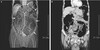

Chron's disease ## Footnote A: Inflammation at the area of the terminal ileum B: Can appreciate the thickened walls, narrow lumen, looks string like

123